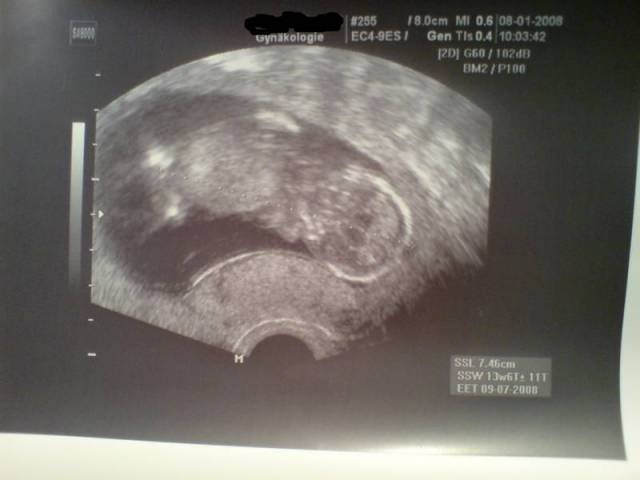

14_1 15. SSW Datum 19.05.2008 15. SSW

14_2 15. SSW Datum 19.05.2008 15. SSW